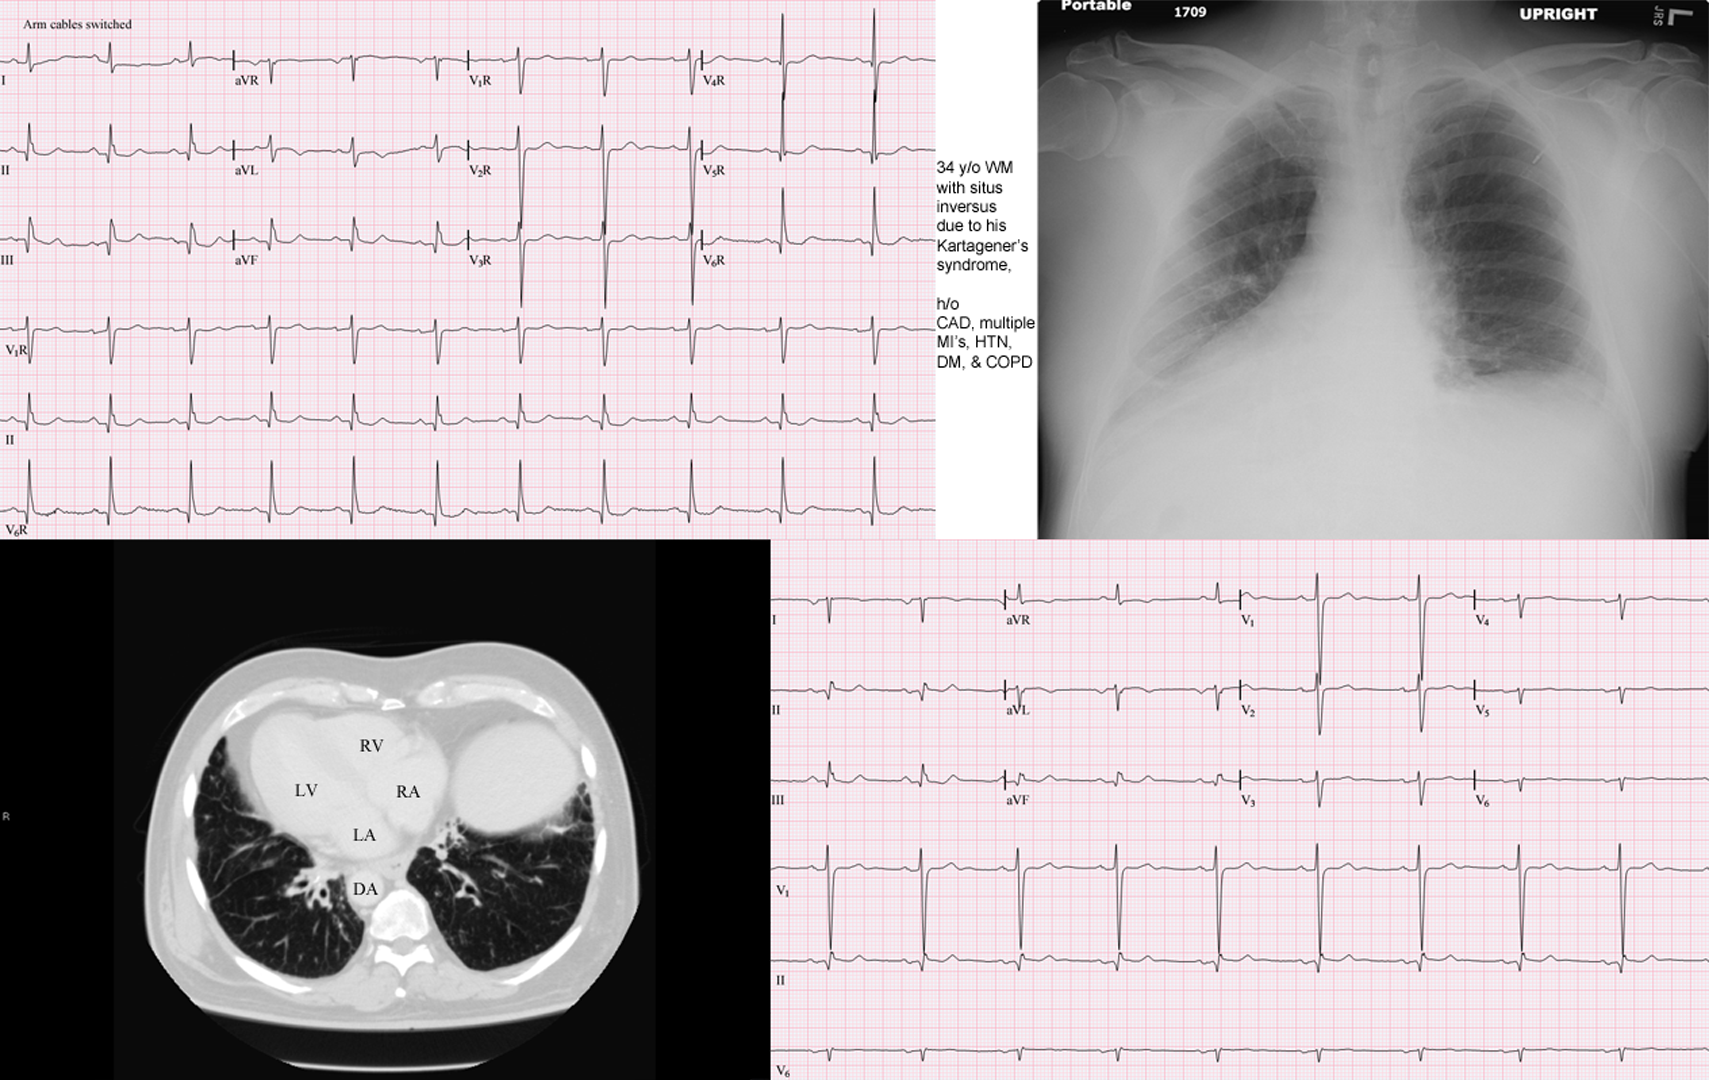

Синдром зиверта картагенера